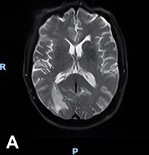

Diagnostic Testing. One day after admission, an initial brain MRI revealed a necrotic, contrast-enhancing lesion in the right occipital lobe with surrounding vasogenic edema, along with smaller enhancing nodules near the right lateral ventricle and in the left cerebral hemisphere (Figure 1A). Four days following admission, cervical and thoracic spine MRI demonstrated punctate enhancing foci within the proximal spinal cord and pons (Figure 1B), making findings initially suspicious for metastatic disease.

Figure 1A-B. (A) Initial brain MRI shows a necrotic, enhancing lesion with surrounding edema in the right occipital lobe. Several small enhancing nodules are seen near the right occipital and temporal horns in the left hemisphere. (B) Sagittal view of thoracic and cervical MRI with prominent focus at the level of T4 shows punctate enhancing foci scattered within the proximal spinal cord and pons, findings suspicious for metastatic disease.